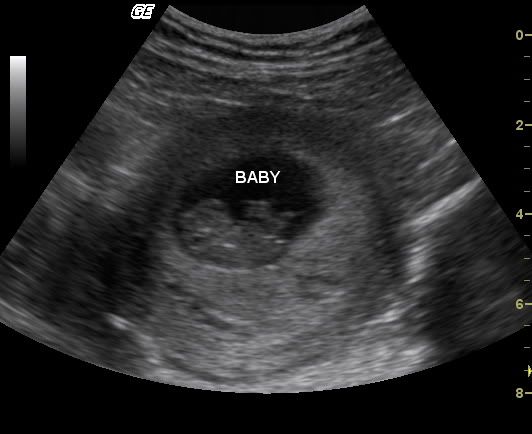

Yesterday we visited the OB for the last ultrasound to determine what we're having...

And its a boy!

Charles Sloan

I really like the yawn, but I still need to get them printed... maybe this weekend.